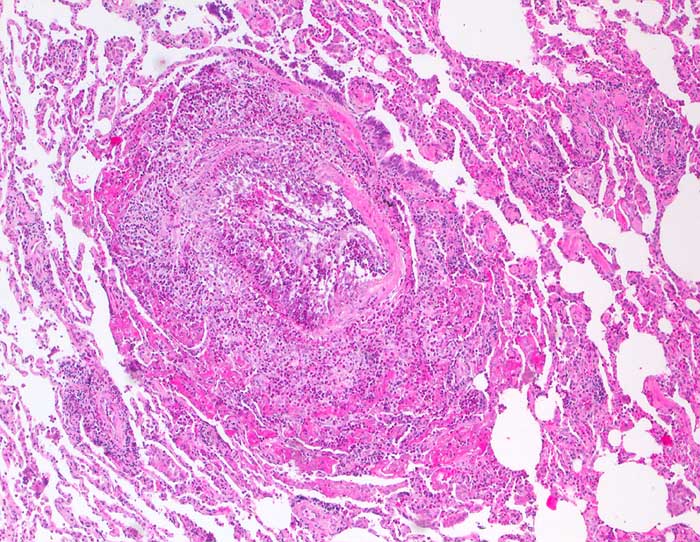

Churg Strauss Vaskulitis

Lunge

Destruktive eosinophile Vaskulitis einer kleinen Arterie.

Der morphologische Befund ist klassisch für ein Churg-Strauss-Syndrom und passt auch zu der Anamnese eines mehrjährigen Asthmas mit aktueller Bluteosinophilie und IgE-Erhöhung. Der Befund könnte im Zusammenhang stehen mit einer ca. seit drei Monaten bestehenden Therapie mit Leukotrien-Rezeptorantagonisten, welche nach Berichten aus der Literatur ein Churg-Strauss-Syndrom möglicherweise demarkieren können.

Histologie

100